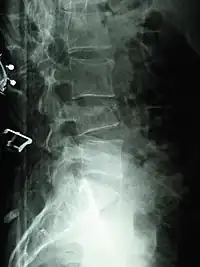

X-ray of the lumbar spine with a compression fracture of the third lumbar vertebra.

A compression fracture is a collapse of a vertebra. It may be due to trauma or due to a weakening of the vertebra (compare with burst fracture). This weakening is seen in patients with osteoporosis or osteogenesis imperfecta, lytic lesions from metastatic or primary tumors,[1] or infection.[2] In healthy patients, it is most often seen in individuals suffering extreme vertical shocks, such as ejecting from an ejection seat. Seen in lateral views in plain x-ray films, compression fractures of the spine characteristically appear as wedge deformities, with greater loss of height anteriorly than posteriorly and intact pedicles in the anteroposterior view.[3]

Compression fractures are usually diagnosed on spinal radiographs, where a wedge-shaped vertebra may be visible or there may be loss of height of the vertebra. In addition, bone density measurement may be performed to evaluate for osteoporosis. When a tumor is suspected as the underlying cause, or the fracture was caused by severe trauma, CT or MRI scans may be performed.